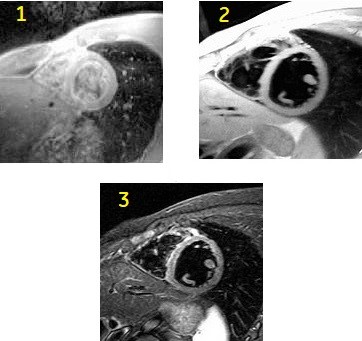

FSE Double and Triple IR scan

Use Double and Triple IR scans to visualize cardiac anatomy, myocardial wall masses, valve leaflets, and black blood. FSE Double and Triple IR images are very sharp images in comparison to SSFSE Double and Triple IR scans, but they are longer acquisitions.

| Number | Description |

|---|---|

| 1 | FSE short axis cardiac image |

| 2 | Double IR short axis cardiac image |

| 3 | Triple IR short axis cardiac image. |